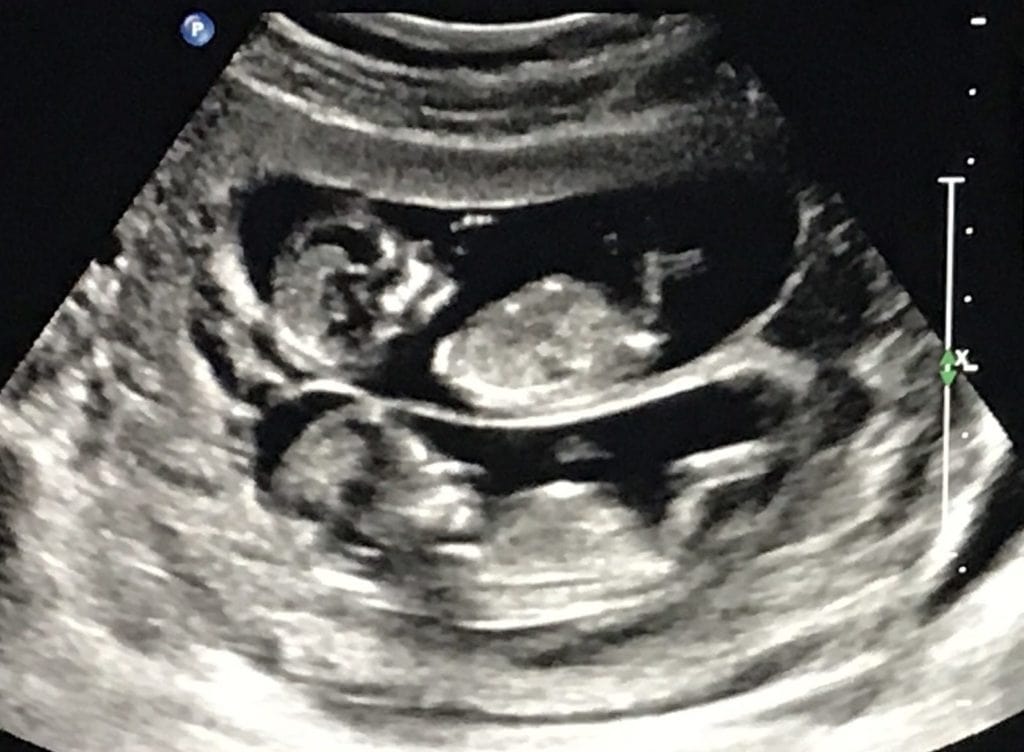

Ultrasound Photos at 12 Weeks Pregnant With Twins